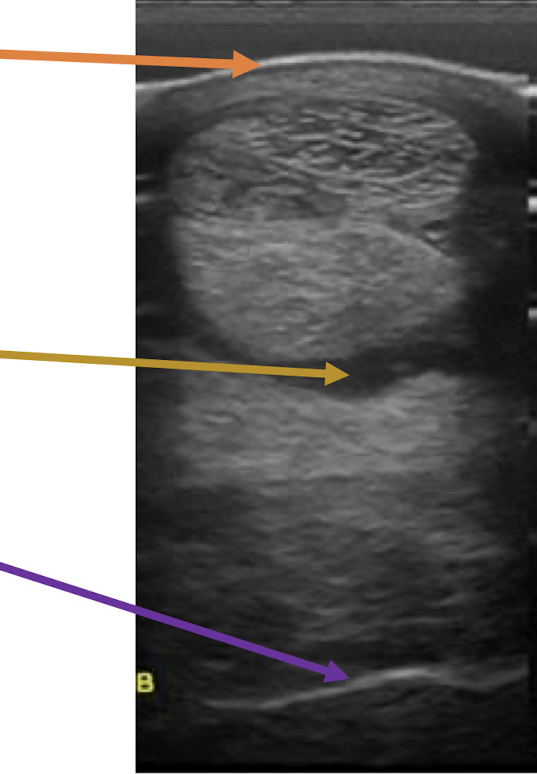

What is the orange arrow showing?

skin

What is the yellow arrow showing?

fluid

What is the purple arrow showing?

bone